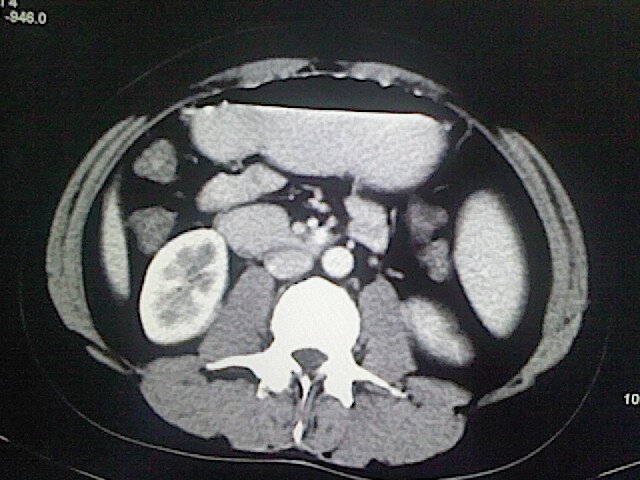

以下是引用卜一在2009-3-14 9:49:00的发言:[br]胆囊萎缩,胆囊壁不规则增厚,内部结构模糊,增强明显强化。另:肝左叶外侧段肝囊肿。支持:慢性胆囊炎!高度可疑:胆囊癌!

以下是引用余辉在2009-3-14 8:48:00的发言:[br]1)慢性胆囊炎。2)肝左叶外侧段肝囊肿。3)脂肪肝。[br]支持,胆囊萎缩,密度增高,不知b超具体有何提示,钙胆汁?结石?

以下是引用jiangjing在2009-3-14 10:18:00的发言:[br]1)慢性胆囊炎。2)肝左叶外侧段肝囊肿。3)脂肪肝。4.】建议行肝功能检查